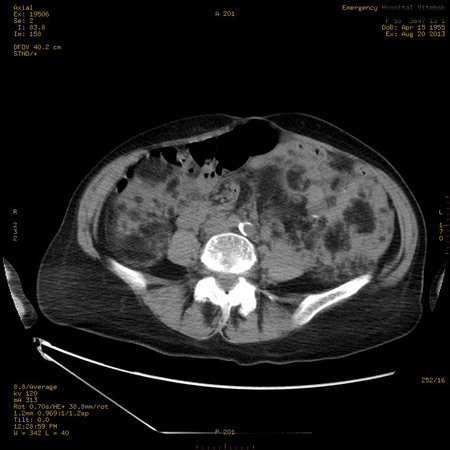

Пожилая женщина с нормальными мочевиной и креатинином.

Ангиомиолипоматоз почек , думаю компонент туберозного склероза.

Да, туберозный склероз.

Случай консультирован на кафедре радиологии Католического университета г.Лёвен (Бельгия) - зав каф. профессор Р.Оуен.